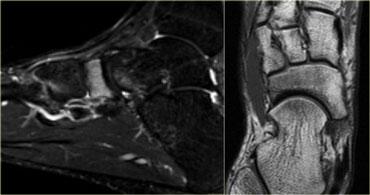

Bên trái là hình ảnh của bệnh nhân nữ 28 tuổi với khởi phát đau gần đây tại vùng xương đốt bàn chân thứ hai.

Tại thời điểm thăm khám, phim X-quang âm tính với gãy xương đốt bàn chân thứ hai.

Chuỗi xung MRI STIR (Short TI Inversion Recovery) cho thấy tăng tín hiệu tủy xương và phần mềm xung quanh, gợi ý phù tủy xương là hậu quả của gãy xương do stress.